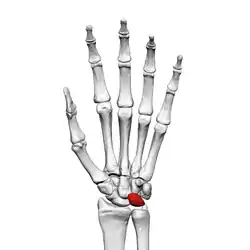

![]() Left hand anterior view (palmar view). Lunate bone shown in red. | |

The lunate bone (semilunar bone) is a carpal bone in the human hand. It is distinguished by its deep concavity and crescentic outline. It is situated in the center of the proximal row carpal bones, which lie between the ulna and radius and the hand. The lunate carpal bone is situated between the lateral scaphoid bone and medial triquetral bone.

The lunate is a crescent-shaped carpal bone found within the hand. The lunate is found within the proximal row of carpal bones. Proximally, it abuts the radius. Laterally, it articulates with the scaphoid bone, medially with the triquetral bone, and distally with the capitate bone. The lunate also articulates on its distal and medial surface with the hamate bone.[2]: 708 [3]